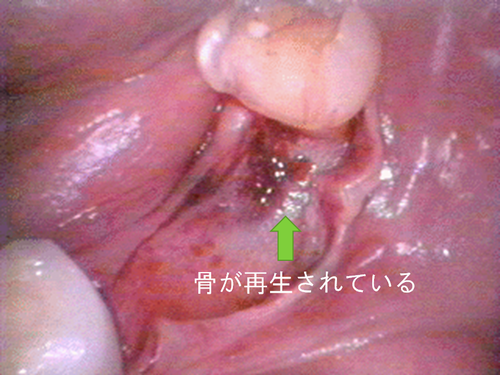

この患者様は、右上の奥歯の歯茎から出血してくるとのことで来院されました。歯周組織検査とレントゲンで診断を行った結果、重度の歯槽膿漏が認められ、保存不可能の為、抜歯になると伝えたところ、入れ歯は絶対に嫌だと言われたので、インプラント治療となりました。CT撮影を行ったところ、上顎洞底までの距離が3ミリ程度しかなかったのですが、骨が固く、フィクスチャーの一次固定が良好だったので、開窓法による上顎洞底挙上術とフィクスチャーの埋入を同時に行いました。約10カ月後に二次手術を行い、上部構造をセットしました。また、右下の臼歯部のブリッジにも大きな二次カリエスが認められ、7番の遠心根が抜歯になり、6番、7番にインプラント治療をしました。